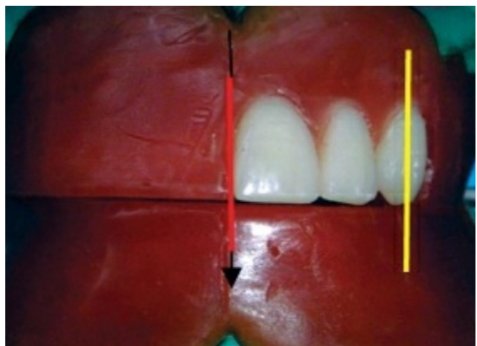

The long axis of the maxillary second molar (blue line) is distally

inclined in relation to the vertical axis (red line) when viewed from the front .

All the cusps are short of the occlusal plane (black line).

The maxillary second molar is slightly buccally inclined when viewed from the front. The buccal surface of the maxillary second molar is barely visible when viewed from the front

When viewed from:

Front: Long axis slopes buccally more steeply than first molar.

Side: Long axis slopes distally more steeply than first molar.

Occlusal plane: Only mesiopalatal cusp is nearest to occlusal

plane

Guidelines for anterior teeth setting are marked on the cast and the land area of the cast.

I. The centre of the incisive papilla (marked in red)

II. A line is drawn along the midline of the cast through the centre of the incisive papilla (marked in black).

III. A perpendicular line is drawn to the above line through the centre ofincisive papilla till the land area (marked in blue; CPC line).

IV. During setting of maxillary canine, the cuspid tip of the canine should be placed in line with this point

The crest of the lower residual alveolar ridge is marked in red colour along the posterior aspect of the lower cast. A corresponding line is marked on the upper cast in blue